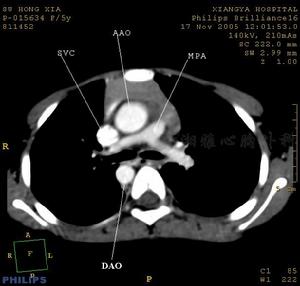

4、X線檢查,右心室擴大,肺動脈園錐隆出,肺門血管陰影減少及纖細。

3、X線檢查注意有無右心室增大、肺動脈段擴張(狹窄後擴張)。肺紋理往往減少或正常。